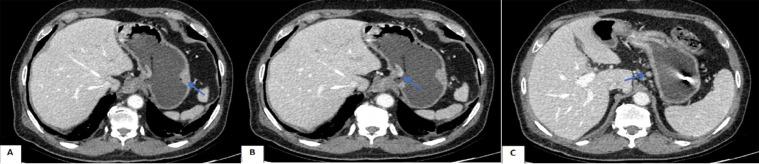

The coexistence of multiple primary malignant tumors in an organ is rare. This includes the extremely rarely reported combination of gastric adenocarcinoma and gastric MALT-type lymphoma as synchronous tumors. We describe a case of a 72-year-old man diagnosed with this combination. He had no remarkable medical history and came to our hospital because of discomfort in the gastric area. Although the biopsy revealed adenocarcinoma only, the microscopic findings after partial gastrectomy incidentally showed additional lymphoma that was subsequently confirmed by immunohistochemistry as MALT-type lymphoma. This case study and literature analysis aims to raise awareness of the possibility of synchronous malignant neoplasm in the stomach to enhance preoperative diagnosis.

一个器官内存在多种原发性恶性肿瘤的情况较为罕见。这包括极为罕见的胃腺癌与胃黏膜相关淋巴组织(MALT)型淋巴瘤同时发生的病例报道。我们描述了一名72岁男性被诊断为此种组合病例。他既往无显著病史,因胃部不适前来我院就诊。尽管活检仅显示为腺癌,但部分胃切除术后的显微镜检查结果意外发现了额外的淋巴瘤,随后经免疫组织化学证实为MALT型淋巴瘤。本病例研究及文献分析旨在提高对胃内同时发生恶性肿瘤可能性的认识,以加强术前诊断。